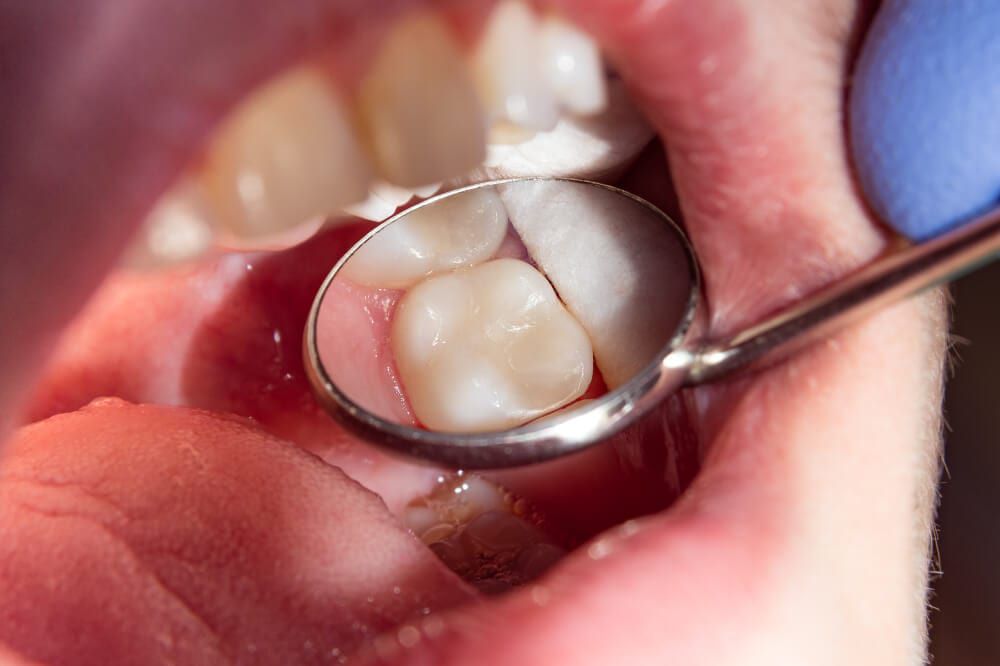

DİŞ DOLGUSU

Diş dolgusu, çürük veya hasar görmüş diş dokusunun temizlenerek oluşan boşluğun dolgu malzemesiyle kapatılması işlemidir.